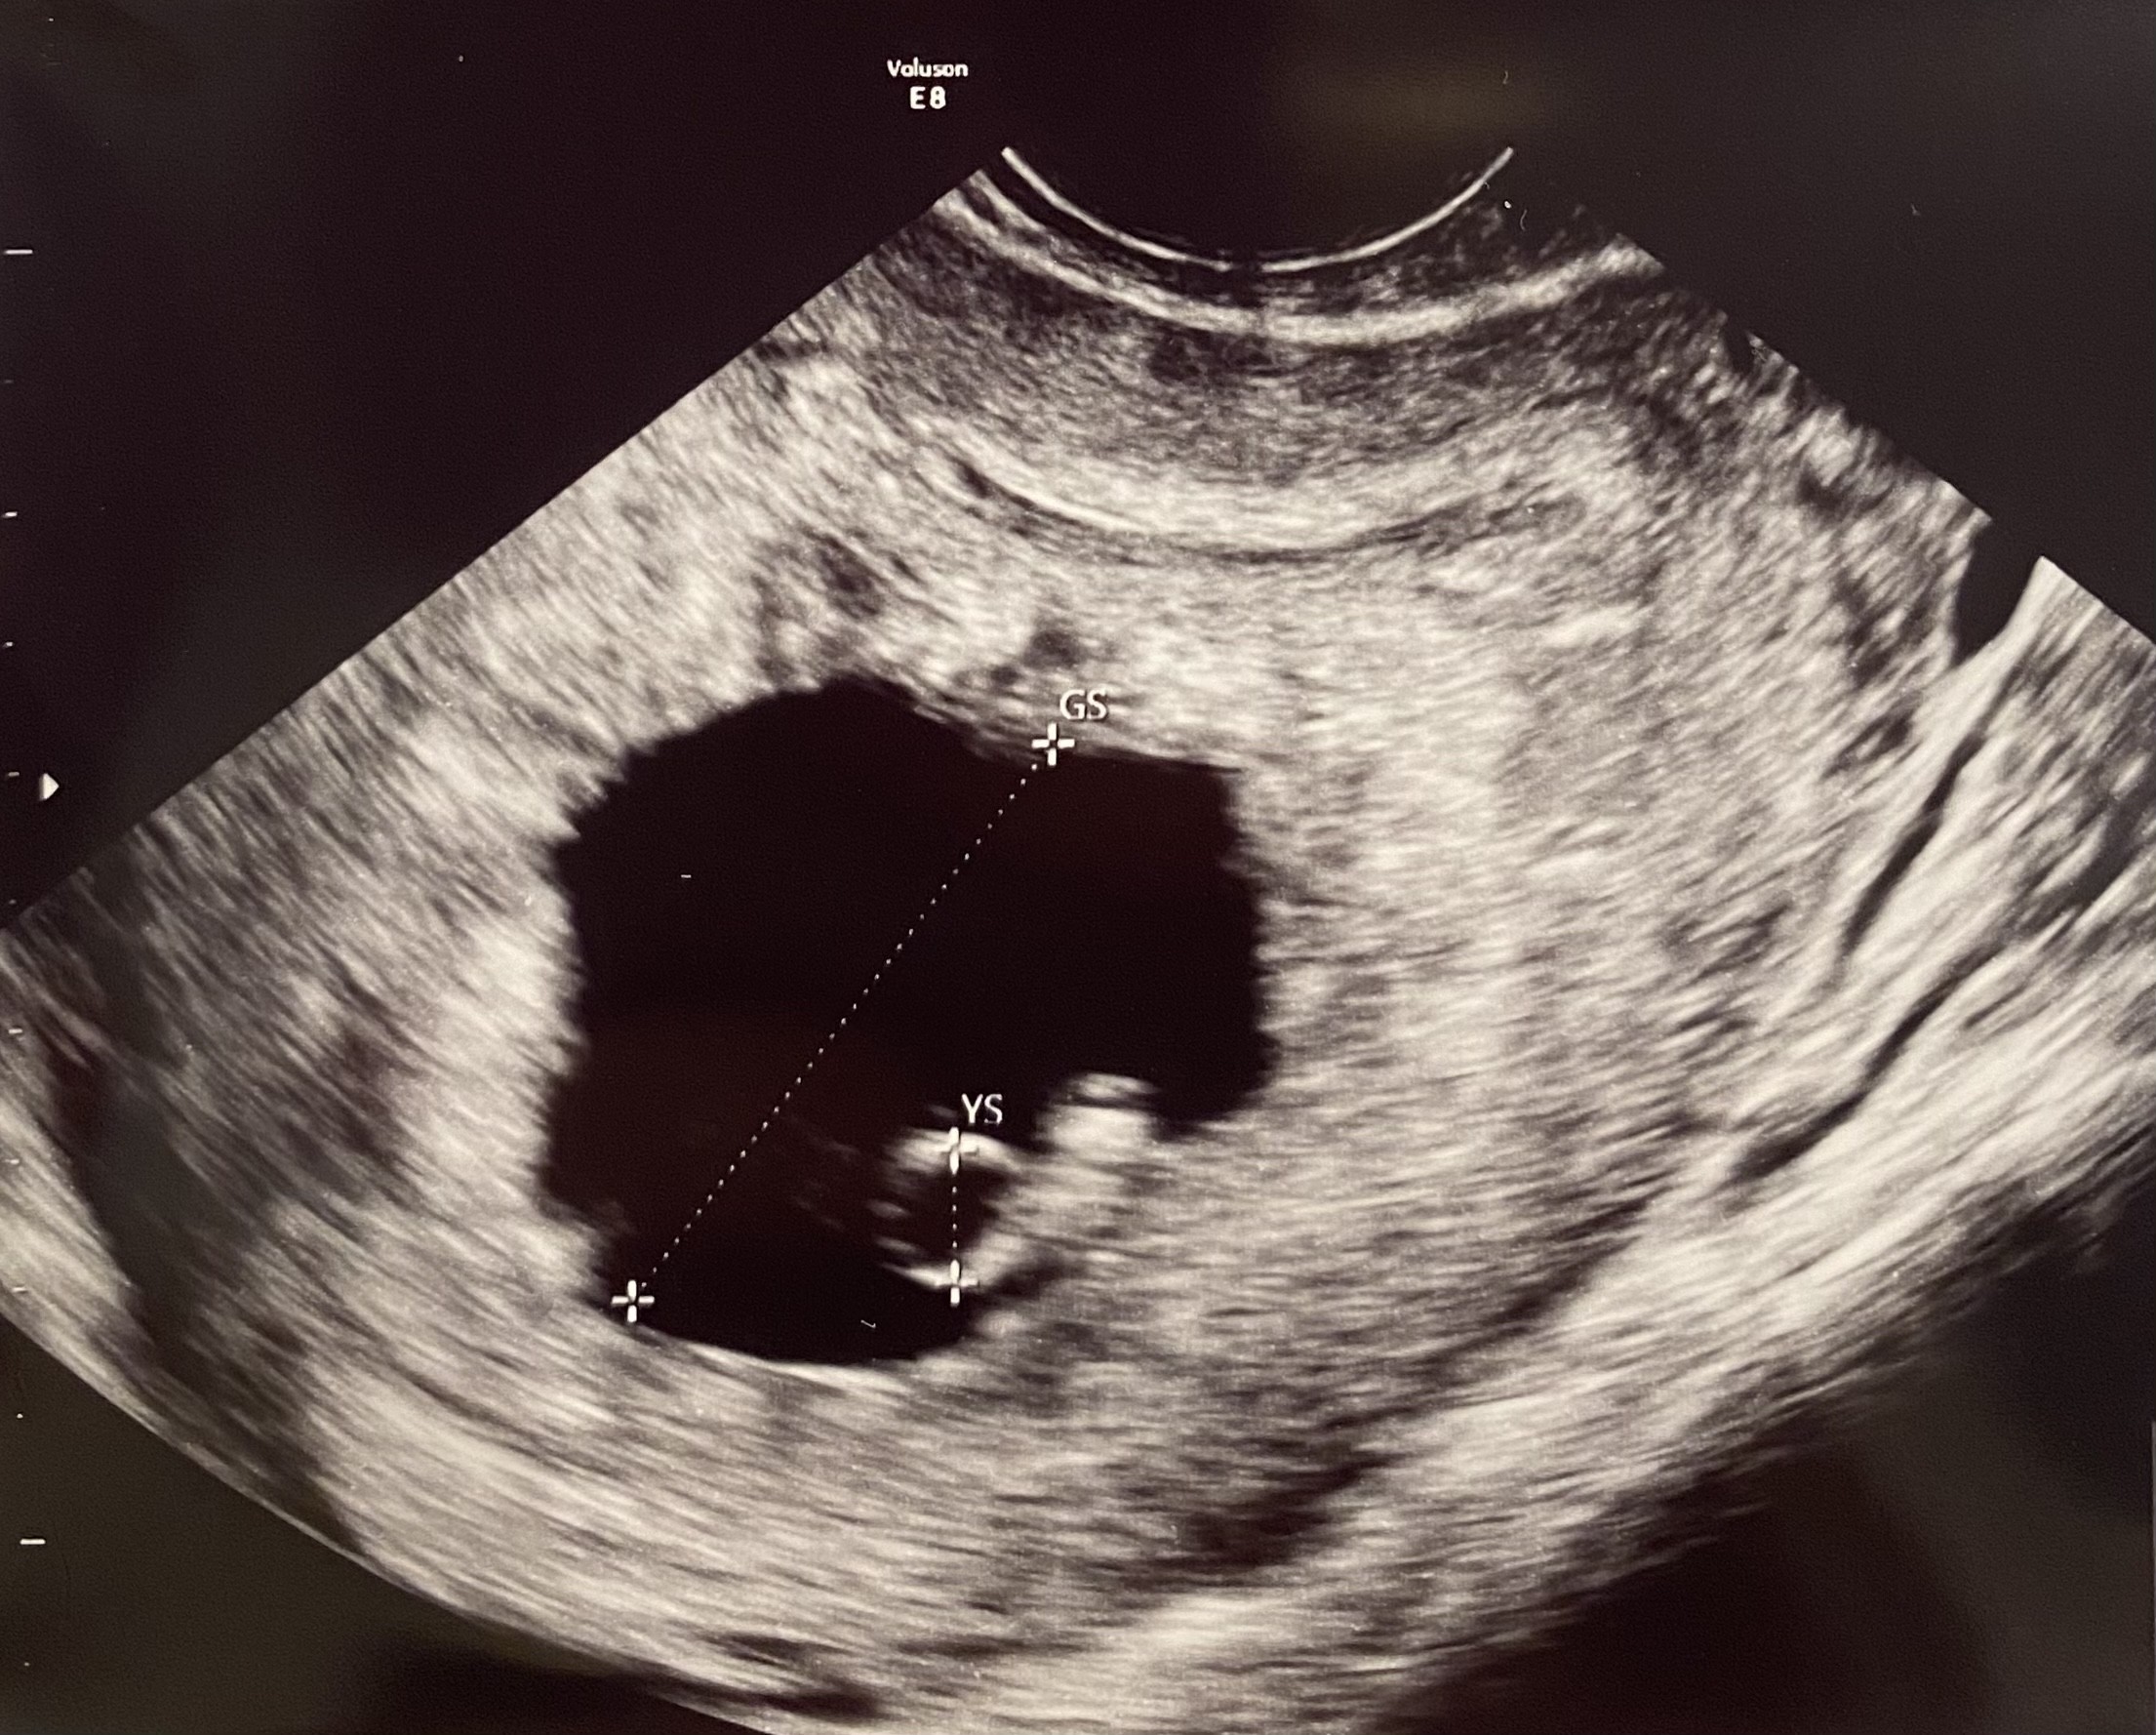

W ostatnim usg wg OM 7tc a wg usg 6tc lekarz nagle zauważył w jednym pęcherzyku ciążowym dwa ciałka żółte, ale tylko jeden widoczny zarodek z bijącym sercem, drugie cialko zolte znajduje się tak jakby przy ścianie pecherzyka i zupełnie nie widać zarodka. Lekarz powiedział że to syndrom zanikającego bliźniaka. Czy któraś z Was to przezyla (ciąża jednokosmowkowa) i czy drugi zarodek rozwijał się normalnie i urodziła zdrowe dziecko?

załączam obraz z usg.